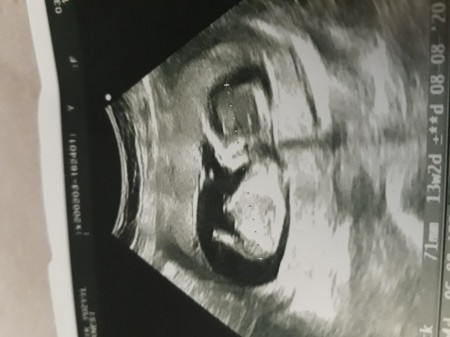

13.haftadayım dr çıkıntı göremiyorum kiz gibi emin değilim dedi.  Yanılabilirmi  13 te belli olmazmi cinsiyet

Bu kiz  mi şimdi? Ben erkek dedim ama bilemedim... 15ten önce genital organ oluşmuş olmuyor ki  :)

Evet 12 haftada oluşmuş oluyor tamamen

Tamam ama tespit edemezler tatlım tam... Allah gonlundekini kaderine yazsın